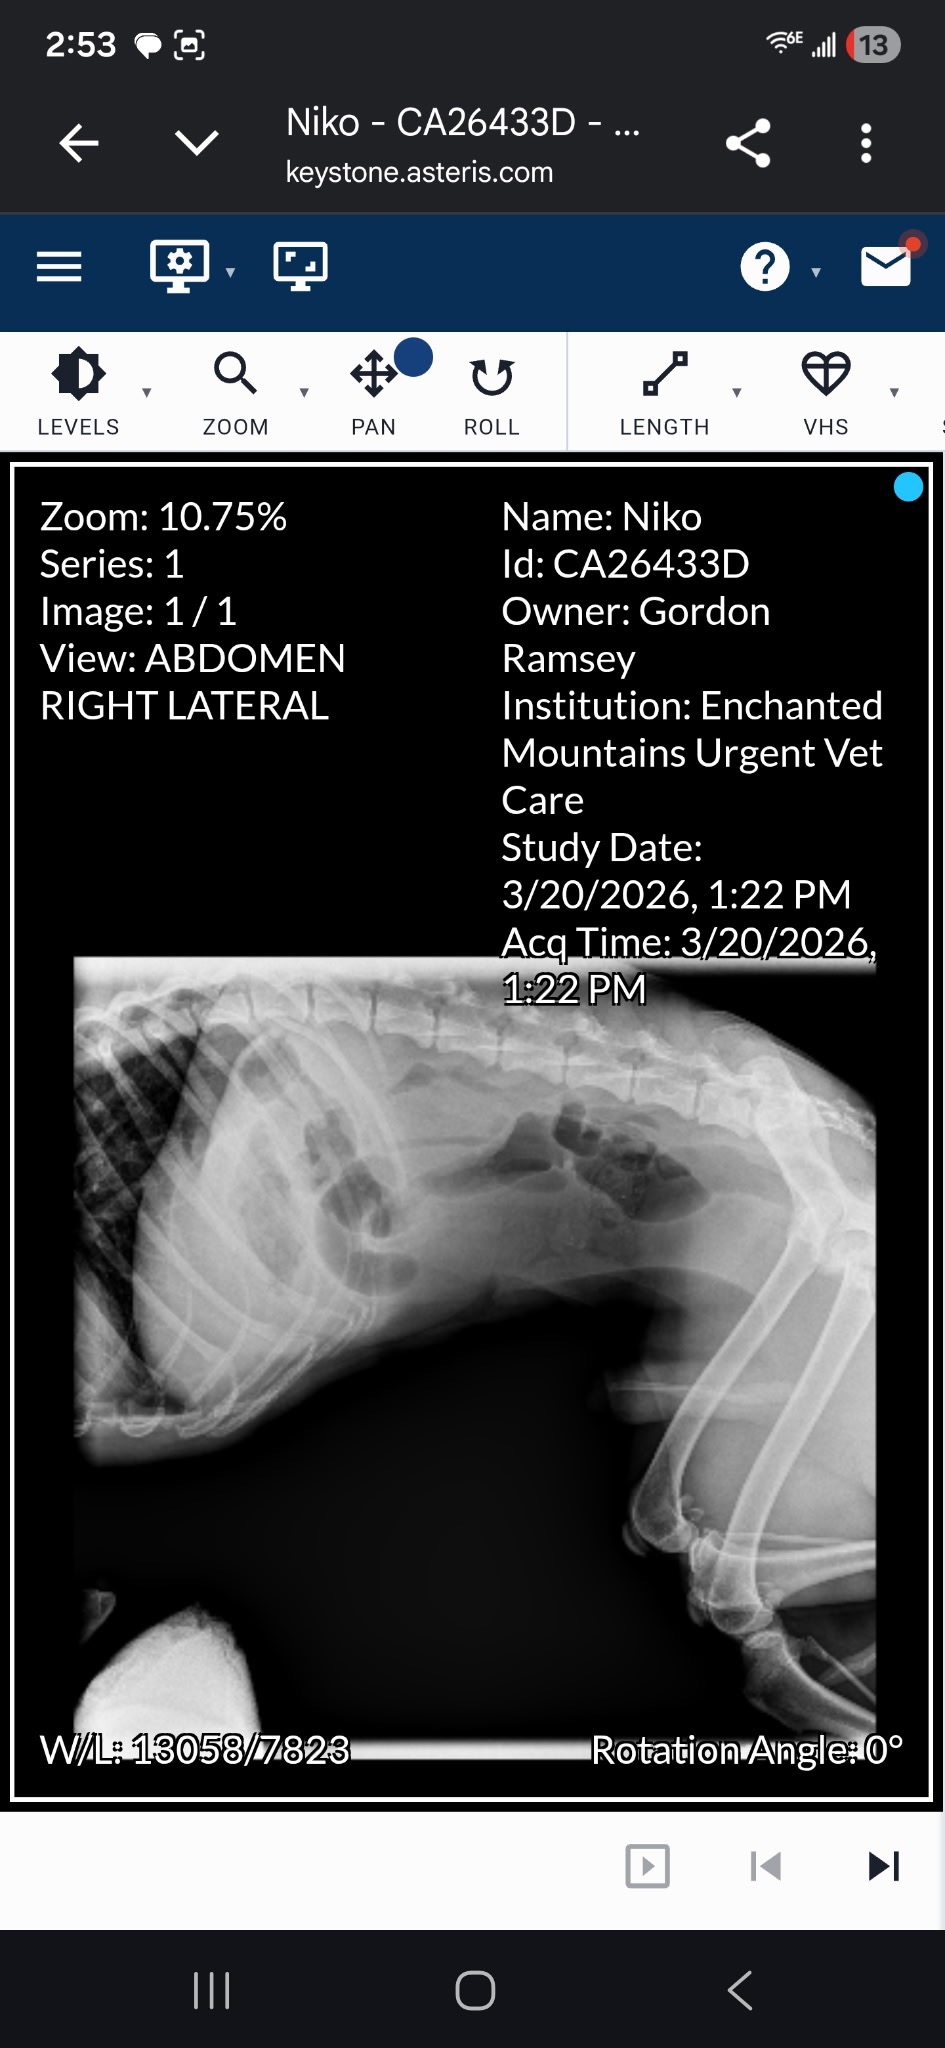

So, Niko does have a severe blockage and needs EMERGENCY SURGERY due to eating a “foreign object,” and he now has a fever. We either have to put him down (he is 1 year old) or pay $5,000 to help him, and at this time, we do not have all of it. He is now home with us to say goodbye if we cannot help him and have to take him back to be put down.